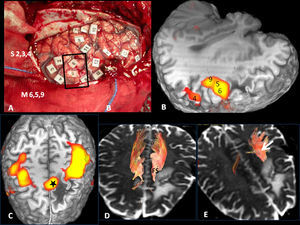

The cortical areas implicated in language (Fig. 1) correlated with cortical stimulation (Table 2) were:

Frontal areas: lower frontal circumvolution (Broca's area), triangular and opercular pars; motor facial cortex (lowest margin of ascending frontal circumvolution); premotor cortex (anterior to the motor facial cortex); supplementary motor area (medial to the most cranial part of the precentral groove).

Temporoparietal areas: left posterior temporal cortex: posterior third of the superior and meddle temporal circumvolutions; lower left parietal lobe: angular and supramarginal circumvolutions.

Occipitotemporal basal areas: lower temporal and fusiform circumvolutions. They are areas related with visual recognition, specialized in identification of the form of words or objects, such as the left turn (“visual word form area” and “visual object-form area”).

Volumetric functional MR. (A) Frontal cortical areas, (B) temporoparietal areas and (C) basal occipitotemporal areas implicated in language. 1: Broca's area; 2: Premotor cortex; 3: Motor facial cortex; 4: Supplementary motor area; 5: Wernicke's area; 6: Visual word form area. **Auditory association areas.

Low-grade oligodendroglioma in the left insular region. 25-Year-old patient with a history of a traffic accident and paresthesia in the upper right limb. (A) Left insular lesion with a tumoral volume of 25cm3. (B) In the perfusion map, he has a relative brain blood volume (RBV) of 1.3. (C) In the spectroscopy-MR study, he presents an increase of cholina and myoinositol, and a discrete reduction of N-acetyl-aspartate. These are data indicative of a low-grade glioma. (D) The T1 sagittal plane shows the relation of the lesion with frontal operculum. (E) The 3D tractography shows an infiltration of the anterior third of the lower frontooccipital fasciculus (discontinuous arrow). (F) The arcuate fasciculus is complete.

Cortical correlation between functional MR and the surgical electrical mapping in the same patient from Fig. 4. (A) Intraoperative mapping. Patient in right lateral recumbent position. 4: Motor facial cortex; 3: Premotor cortex; 5, 6: Broca's area; 8: Frontal eye field. Correlation with functional MR (B, C and D): activation areas coincidental with cortical mapping. *Supplementary motor area. A: anterior; P: posterior.

Subcortical correlation between diffusion tensor image (DTI) and the surgical electrical mapping in the same patient from Figs. 4 and 5. (A) Intraoperative subcortical mapping. Patient in right lateral recumbent position. 41: Lower frontooccipital fasciculus (LFOF). (B) Cortical correlation with functional MR: 3: premotor cortex; 5: Broca's area; 8: frontal eye field. 3D-DTI sagittal reconstructions of LFOF. (C and D) The posterior margin of the LFOF (41) (arrow) limits posterior resection of tumor.